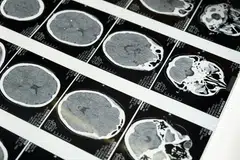

For symptomatic patients with risk factors, there are now safe and accurate diagnostic choices beyond having a catheter inserted invasively into your arteries to diagnose blocked heart arteries. Special X-rays called Computed Tomography (CT) scans of the heart arteries have been used for more than two decades to detect the presence of blocked arteries non-invasively. However, the advent of a new technology, Photon Counting CT (PCCT), has enabled highly accurate diagnoses of heart artery disease with up to 0.2 mm resolution within seconds, and without the risks and high costs associated with invasive coronary angiography.

Unlike other conventional CT scans, which have limited accuracy in the presence of stents or calcium in the heart arteries, PCCT is able to provide high-resolution images with minimal artifacts. Published studies have shown that invasive coronary angiogram, whether via the wrist artery or groin artery, carries a real risk of silent stroke detectable on magnetic resonance imaging. Similarly, the use of PCCT can detect the presence of neck and brain artery stenoses and aneurysms without the need for invasive tests.